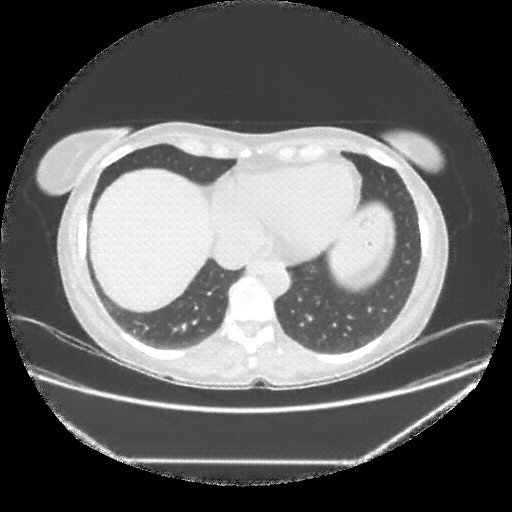

Original NATIVE CT scan (input)

Full window (WL 1023.5, WW 4095 β†’ Low βˆ’1024, High +3071)

Lung window (WL -600, WW 1500 β†’ Low βˆ’1350, High +150)

Mediastinum window (WL 40, WW 400 β†’ Low βˆ’160, High +240)